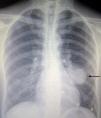

Se trata de una paciente de 41 años de edad, de nacionalidad china, que tras un cuadro de tos seca comienza de forma aguda con dolor torácico1 izquierdo y disnea de esfuerzo. Ante dicha clínica acude a urgencias, donde se realiza radiografía de tórax, que revela la presencia de una masa pulmonar infrahiliar izquierda (fig. 1). La PET-TC muestra una masa infrahiliar de 59×42×50mm (fig. 2) y 7 nódulos pulmonares de entre 1 y 12mm. Ni la masa ni los nódulos presentan actividad metabólica incrementada. Se procede a exéresis íntegra de la masa por neumotomía. Como complicación aislada presentó hemotórax en el postoperatorio y fue necesaria una reintervención quirúrgica, con evolución posterior satisfactoria, y pudo ser dada de alta a domicilio a las 72h de la primera intervención. La histología confirma un neumocitoma de 65mm de diámetro máximo, de patrón mixto, con predominio sólido con áreas pseudopapilares, con ausencia de atipia, mitosis o necrosis2. Fueron necesarias 2 intervenciones quirúrgicas para resecar la totalidad de los neumocitomas, pues presentaba, además del descrito, otros 7 neumocitomas, de menor tamaño, de entre 1 y 12mm, distribuidos en el lóbulo inferior izquierdo, el lóbulo superior izquierdo y el lóbulo inferior derecho.